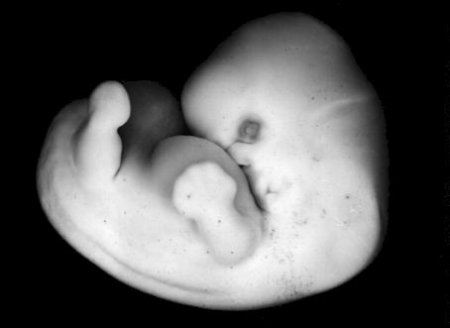

Длина эмбриона — до 12 мм. У плода уже определяется лицо, можно даже различить его ротик, носик и ушные раковины. Головка у зародыша крупная и ее длина на этой неделе уже соотносится с длиной туловища. На этом этапе развития тельце плода уже почти полностью сформировалось.

На восьмой неделе беременности плод продолжает активно развиваться, и его размеры увеличиваются. В этот период длина эмбриона составляет примерно 1,6 сантиметра, а вес — около 1 грамма. На этом этапе формируются основные органы и системы, что делает его критически важным для дальнейшего развития.

Восьмая неделя знаменуется завершением формирования основных структур, таких как сердце, которое теперь уже бьется с регулярным ритмом, и начинает функционировать. Также активно развиваются легкие, печень, почки и кишечник. Внешние признаки также становятся более выраженными: на этом этапе начинают формироваться конечности, и уже можно различить пальцы на руках и ногах.

Кожа плода еще очень тонкая и прозрачная, но уже начинается процесс формирования меланина, который отвечает за цвет кожи. На лице появляются основные черты: глаза, уши и нос начинают принимать более четкие очертания. Внутренние органы продолжают развиваться, и в этот период начинается образование половых органов, хотя пол еще нельзя определить.